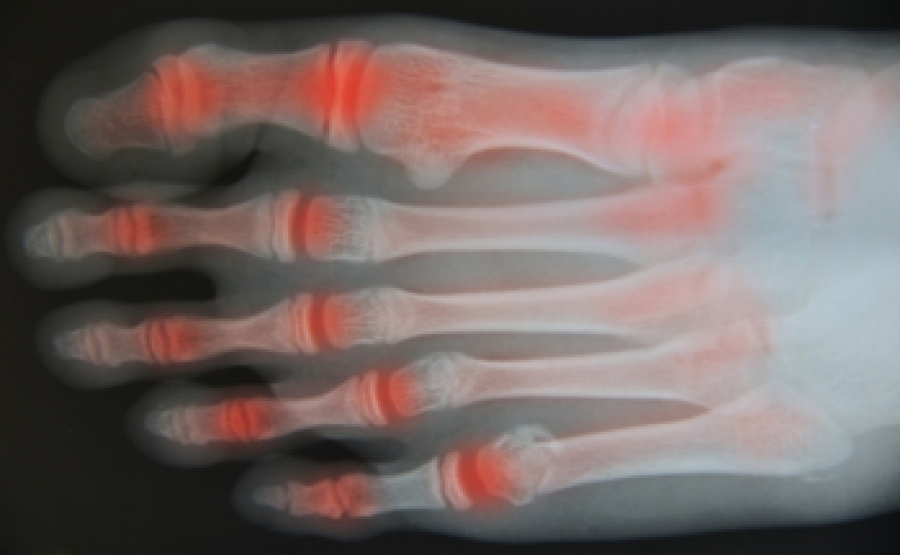

What Are the Signs of Arthritis in Your Feet?

The signs of arthritis can vary.

However, certain common symptoms should be known. These include a loss of sensation in your toes, swelling, and joint pain.